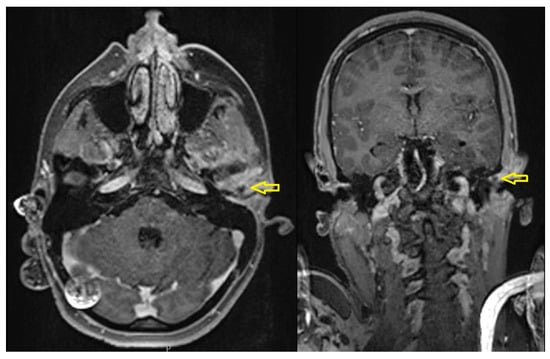

- Case 4

| 4 | Male | 44 | Chronic osteomyelitis of the mandible |

OPG CT/MRI | 13 mm | Incision and drainage of the abscess and surgical curettage | 48 mm |